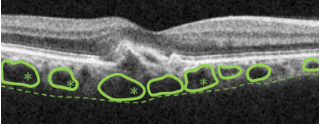

日本人に多い加齢黄斑変性の 病態解明に新展開(鳥取大学医学部より)加齢黄斑変性は老化現象に伴って網膜の中央にある黄斑に障害が生じ、視力の低下や視野の異常を引き起こす疾患です。加齢黄斑変性にはいくつかのタイプがあり、その中でもパキコロイド血管新生黄斑症というタイプは、日本人に比較的多く見られます。このたび、本学部医学科・視覚病態学分野の馬場高志講師らが、パキコロイド血管新生黄斑症の発症にIL-4という因子が関与していることを明らかにしました。IL-4はアレルギー性結膜炎や気管支喘息といったアレルギー性疾患の悪化に関係する因子ですが、加齢黄斑変性の発症に関係する因子として、IL-4 に着目した研究はありませんでした。研究の結果、眼内の IL-4 濃度が高い人は、そうでない人に比べてパキコロイド血管新生黄斑症の発症率が高いことがわかりました。 この研究からIL-4がパキコロイド血管新生黄斑症に関与していることが明らかとなり、今後疾患の原因究明につながることが期待されます。 詳しくは、https://research-er.jp/articles/view/119256 2023.12.29 |